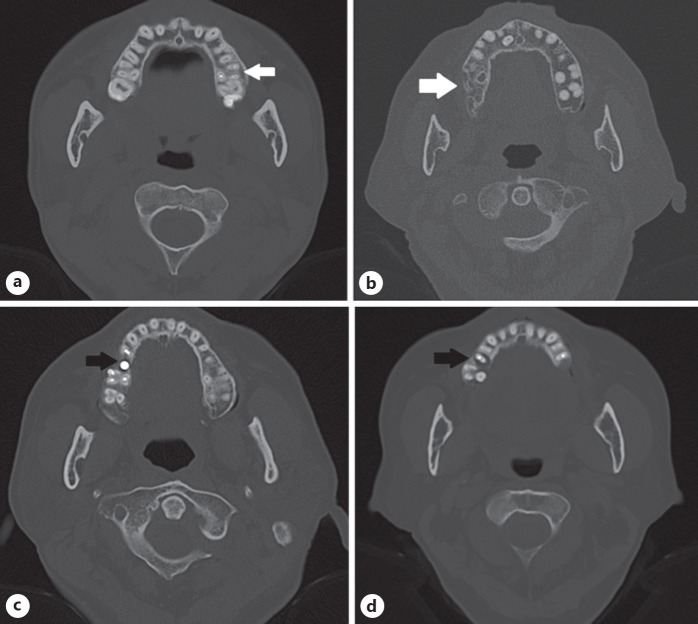

Objectives: This study aimed to investigate the associations between dental treatments and fungal maxillary sinusitis (FMS).

Methods: We retrospectively reviewed medical charts between July 2014 and March 2019. In total, 100 cases of FMS were included in this study. We also recruited 200 patients as a control group in the same period. Therefore, each of the FMS, chronic rhinosinusitis (CRS), and normal sinus groups consisted of 100 patients. We recorded all endodontic treatments (EDTs), tooth extractions, dental implantations, and apical lesions (ALs).

Results: The FMS group had higher incidences of tooth extraction (49% vs. 11%, respectively) and EDT (29% vs. 16%, respectively) compared to the normal sinus group and fewer ALs compared to the CRS group (6% vs. 24%, respectively). There were significant differences between the CRS and normal sinus groups in the extraction rate (53% vs. 11%, respectively) and frequency of ALs (24% vs. 4%, respectively). The dental implantation prevalence rates were similar across all 3 groups.

Conclusion: The rates of tooth extraction were significantly higher in the FMS and CRS groups compared to the normal sinus group. In addition, of the 3 conditions, FMS was related to EDT, and CRS was related to ALs.